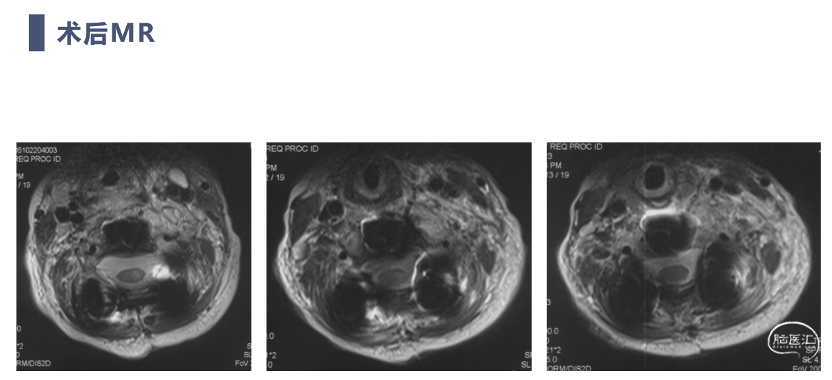

术后MRI

术后复查患者复位满意,颈痛及神经症状消失,但此类患儿骨性结构发育异常,需要密切随诊,观察有无近端或远端交界性后凸发生。

双向牵引后,患者后方小关节仍存在一定绞锁,首先行后路手术,充分松解后方绞锁的关节突。再行前路手术,矫正后凸畸形,前路手术时因患者骨量极少,单纯前路螺钉复位力量弱,借助提拉工具完成良好复位。最后翻身行后路手术完成C2-7后路固定,因患者多数侧块发育异常,双侧C4-5无法置钉,应用椎板钩固定,双侧C2椎弓根直径只有3.2mm,但成功置入了两颗3.5mm螺钉。